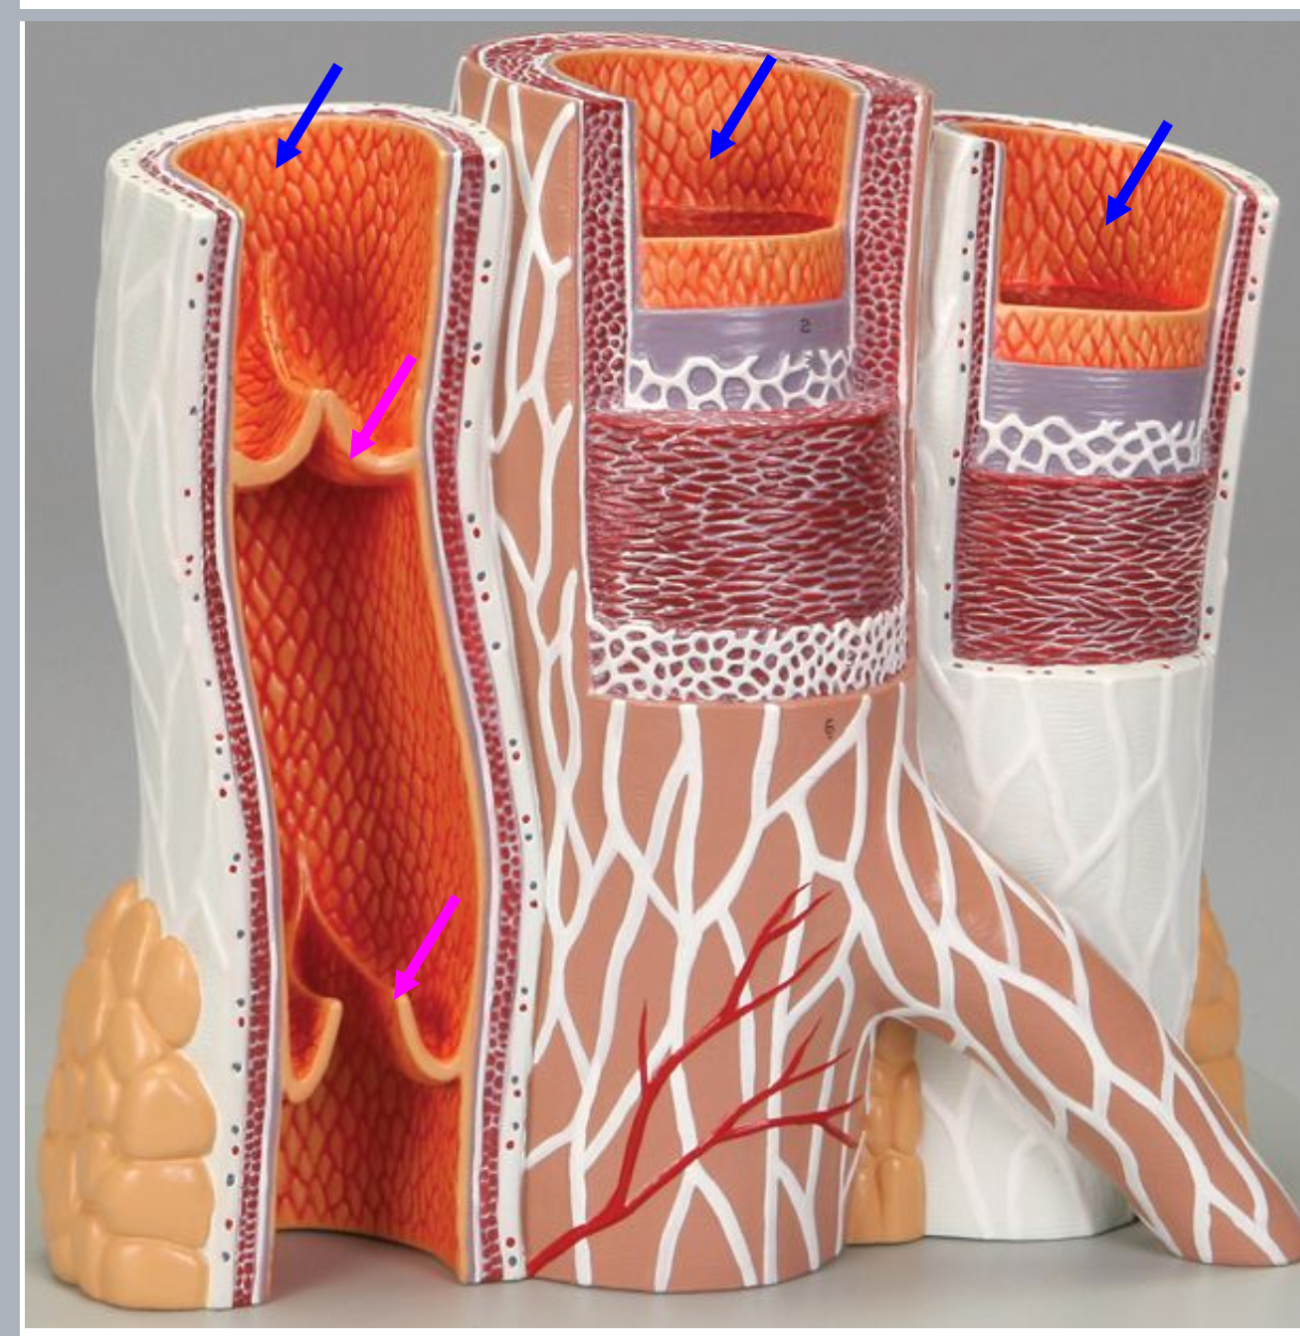

Tunica intima

Name the blue arrow

Lines lumen and release vasoactive chemicals

Function of tunica intima

Venous valves

Name the pink arrow

Prevent backflow of blood

Function of venous valves

Tunica media

Name green arrow

Vasoconstriction and vasodilation

Function of tunica media

Tunica externa

Name the purple arrow

Anchor and bind vessel

Function of tunica externa

Artery

Artery or vein?

Vein

Artery or vein?

Tunica intima

Name the green arrow

Tunica media

Name the yellow

Tunica externa

Name the black